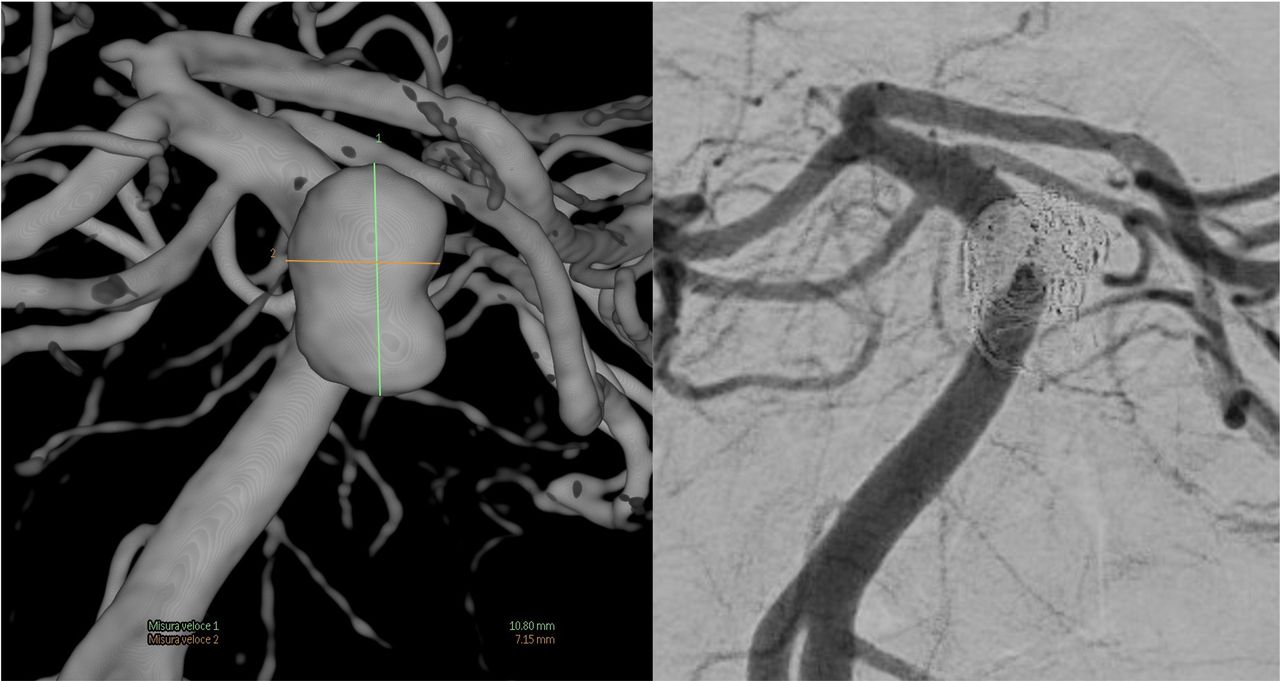

La mia formazione e la mia carriera professionale hanno avuto inizio presso l’Ospedale Niguarda di Milano, dove, per oltre vent’anni, mi sono dedicato con continuità alla diagnosi e al trattamento endovascolare delle patologie vascolari del sistema nervoso centrale. In particolare, ho maturato esperienza nella gestione di aneurismi cerebrali, malformazioni artero-venose, fistole durali, stenosi e trombosi delle arterie e delle vene intracraniche.

Collaborazione con il sito Neuroangio.org, sito di riferimento per i neurointerventisti di tutto il mondo.

https://neuroangio.org/cone-beam-ct-comprehensive-reference-of-principles-and-practice/cone-beam-how-to-do-it-step-by-step-philips/

https://neuroangio.org/cone-beam-ct-comprehensive-reference-of-principles-and-practice/cone-beam-how-to-do-it-step-by-step-philips/cone-beam-ct-philips-complex-aneurysms-flow-diversion-and-stenting/